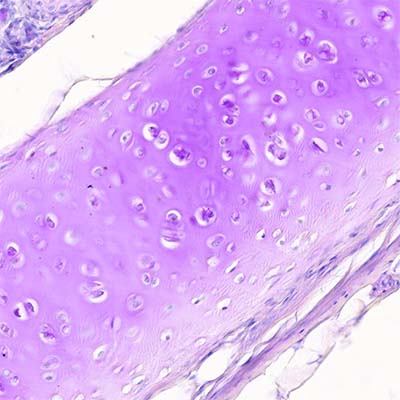

La matriz del cartílago hialino es producida por los condrocitos y contiene tres clases principales de moléculas.

La sustancia fundamental del cartílago hialino contiene tres tipos de glucosaminoglucanos: hialuronato, condroitín sulfato y queratán sulfato. Como en la matriz del tejido conjuntivo laxo, el condroitín sulfato y el queratán sulfato de la matriz de cartílago se unen a una proteína central para formar un monómero de proteoglucanos. El monómero de proteoglucanos más importante en el cartílago hialino es el agrecán. Tiene un peso molecular de 250 kDa.

Debido a la presencia de grupos sulfato, las moléculas de agrecán poseen una carga negativa grande con afinidad por las moléculas de agua. Cada molécula lineal de hialuronato se asocia con una gran cantidad de moléculas de agrecán (más de 300), que están unidas al hialuronato por medio de proteínas de enlace en el extremo N terminal de la molécula para formar grandes aglomeraciones de proteoglucanos. Estas aglomeraciones con mucha carga están unidas a las fibrillas de colágeno de la matriz por interacciones electrostáticas y glucoproteínas multiadhesivas.

El atrapamiento de estas aglomeraciones dentro de la matriz intrincada de f ibrillas de colágeno es la causa de las propiedades biomecánicas singulares del cartílago hialino. La matriz cartilaginosa también contiene otros proteoglucanos (decorina, biglicán y fibromodulina). Estos proteoglucanos no forman agregados pero se unen a otras moléculas y contribuyen a estabilizar la matriz.